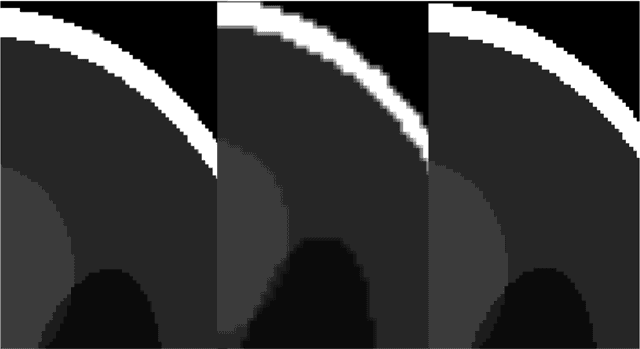

It is a common practice in multimodal medical imaging to undersample the anatomically-derived segmentation images to measure the mean activity of a co-acquired functional image. This practice avoids the resampling-related Gibbs effect that would occur in oversampling the functional image. As sides effect, waste of time and efforts are produced since the anatomical segmentation at full resolution is performed in many hours of computations or manual work. In this work we explain the commonly-used resampling methods and give errors bound in the cases of continuous and discontinuous signals. Then we propose a Fake Nodes scheme for image resampling designed to reduce the Gibbs effect when oversampling the functional image. This new approach is compared to the traditional counterpart in two significant experiments, both showing that Fake Nodes resampling gives smaller errors.